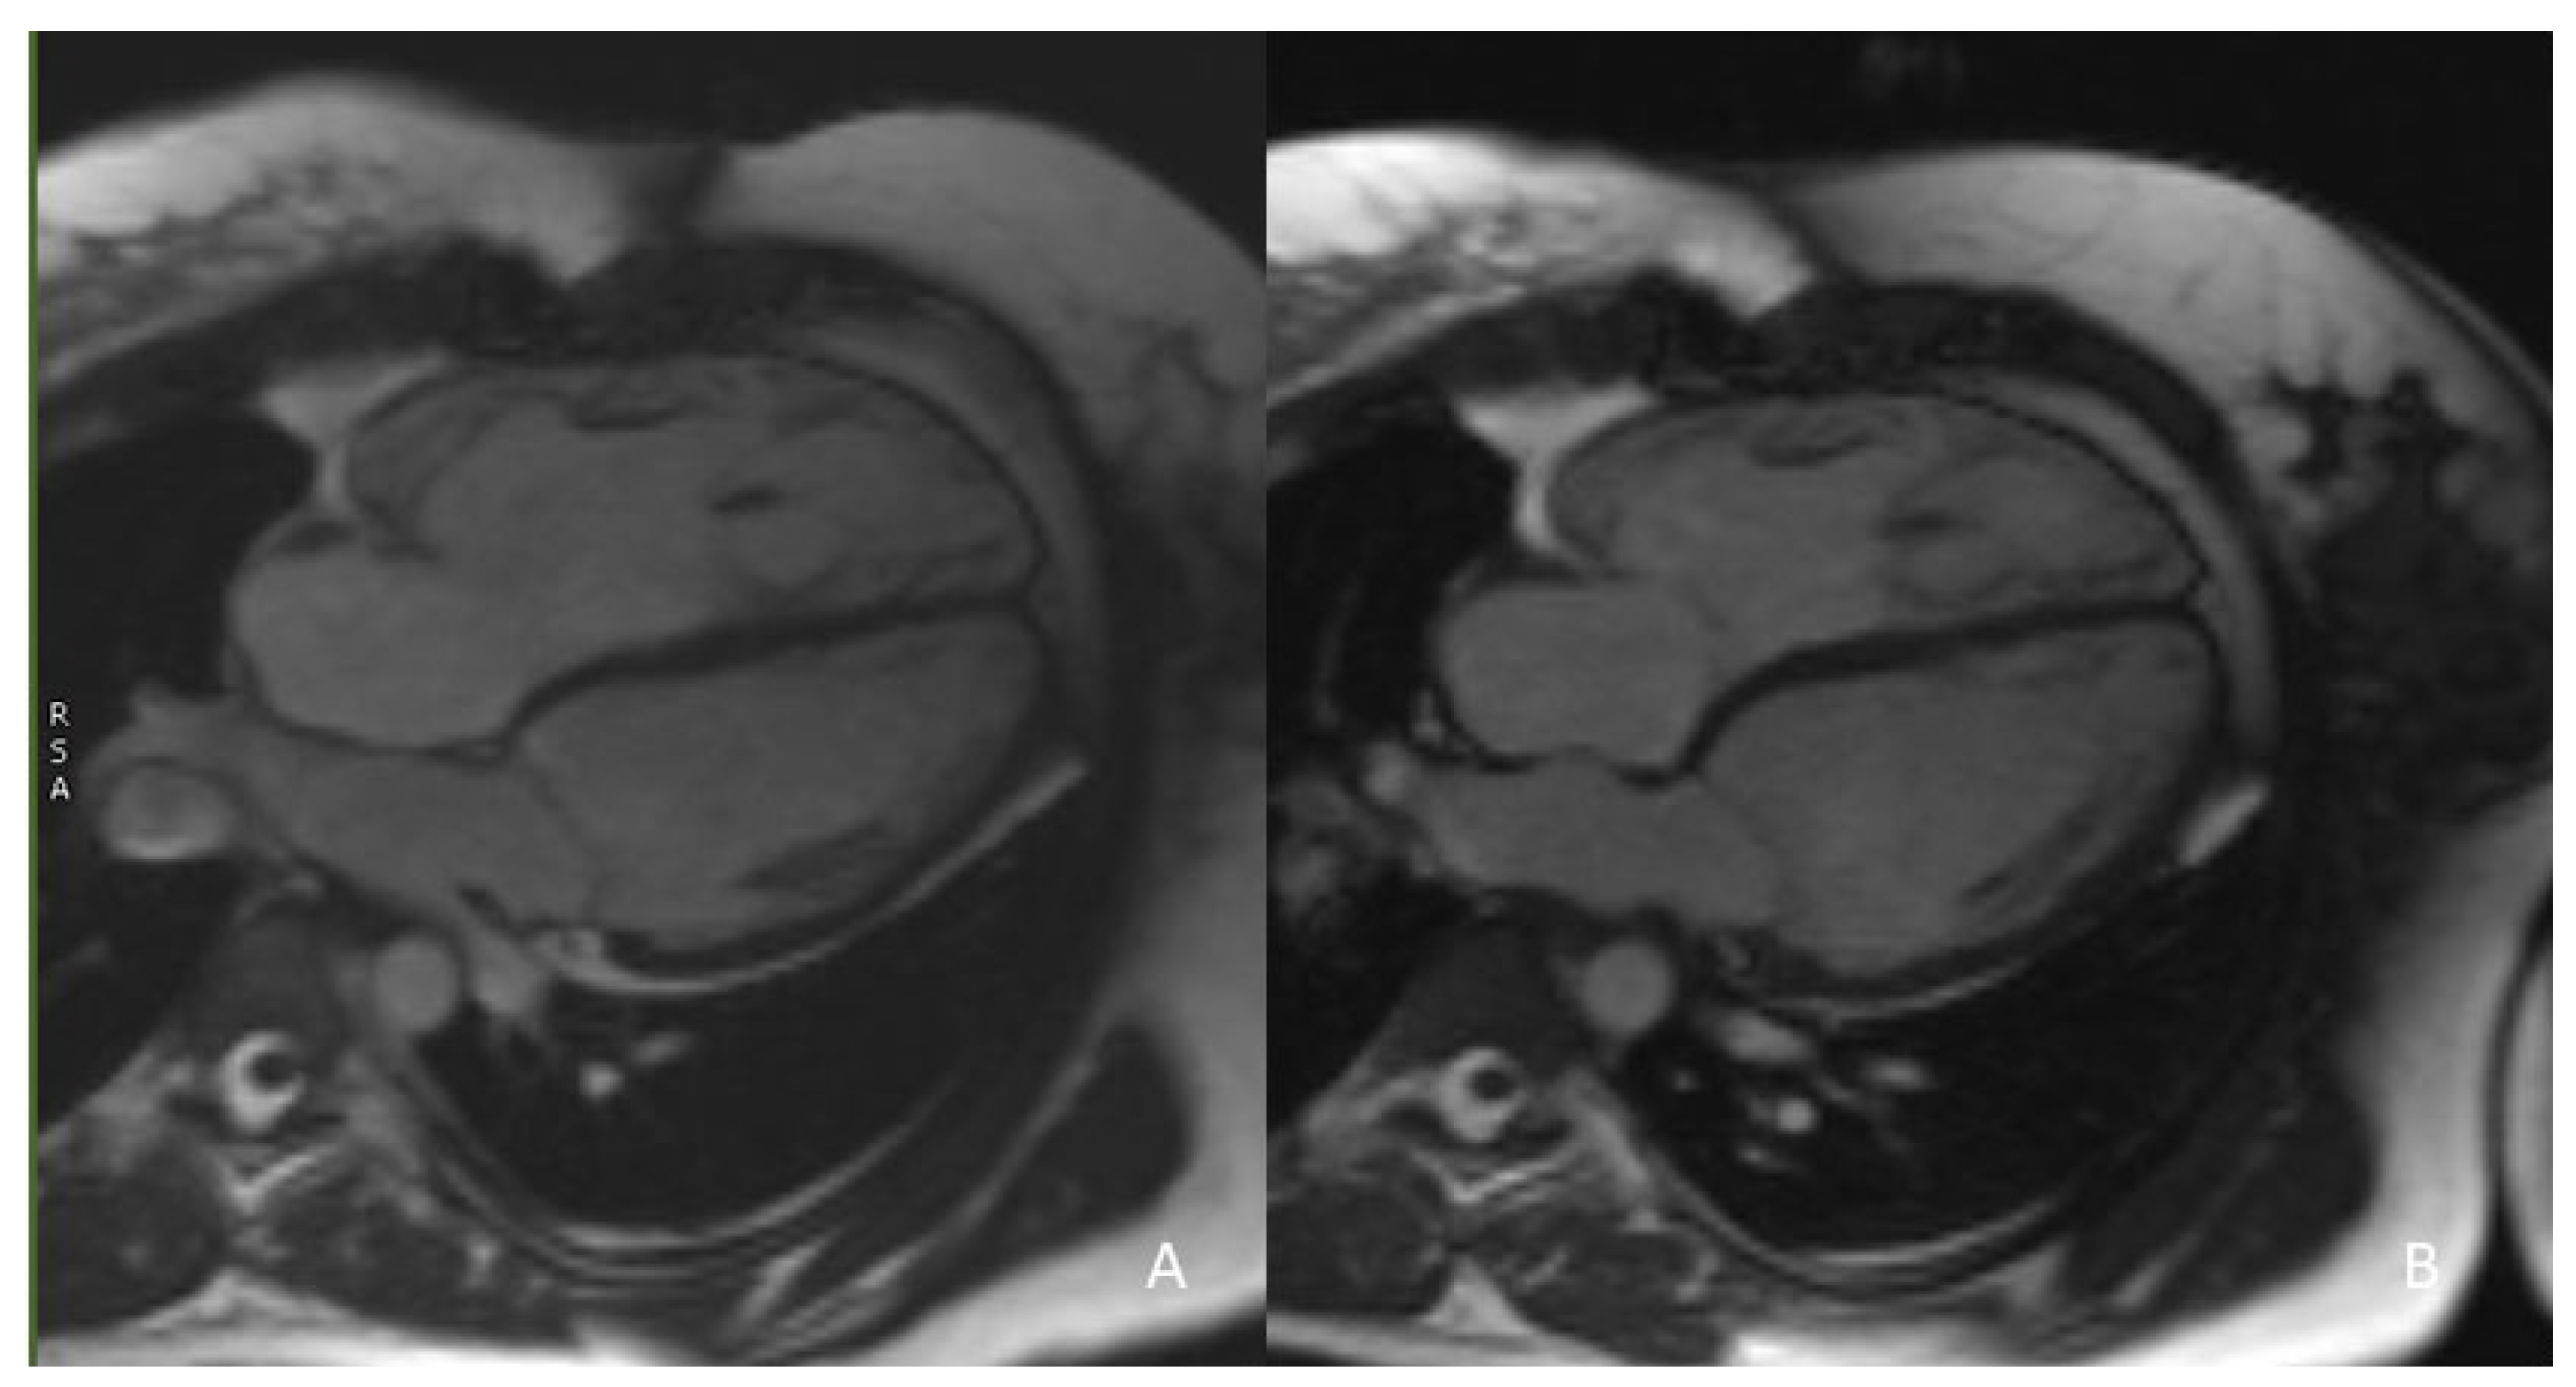

| 2D SSFP cine | 4-chamber Axial (from diaphragm to PA) RVOT RVOT-PA Right and left PA | PROs - Axial slices for volume quantification: 0 mm gap, 6 mm (children) and 8 mm (adults) slice thickness - ECG triggering: RVOT measurements at both end-systole and end-diastole (dynamic sequences) CONs - Breath-hold - High susceptibility to metal artefacts (stents or prothesis): ev. gradient-echo cine sequences are less affected |